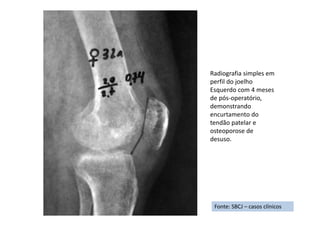

• Diz que houve encurtamento e espessamento do tendão de Aquiles, estas

últimas alterações em decorrência de se manter deambulando apoiado na

ponta do pé direito, desde a retirada do gessado, desenvolvendo, então, um

quadro de síndrome complexa de dor regional - tipo I (sem lesão de nervo

periférico).